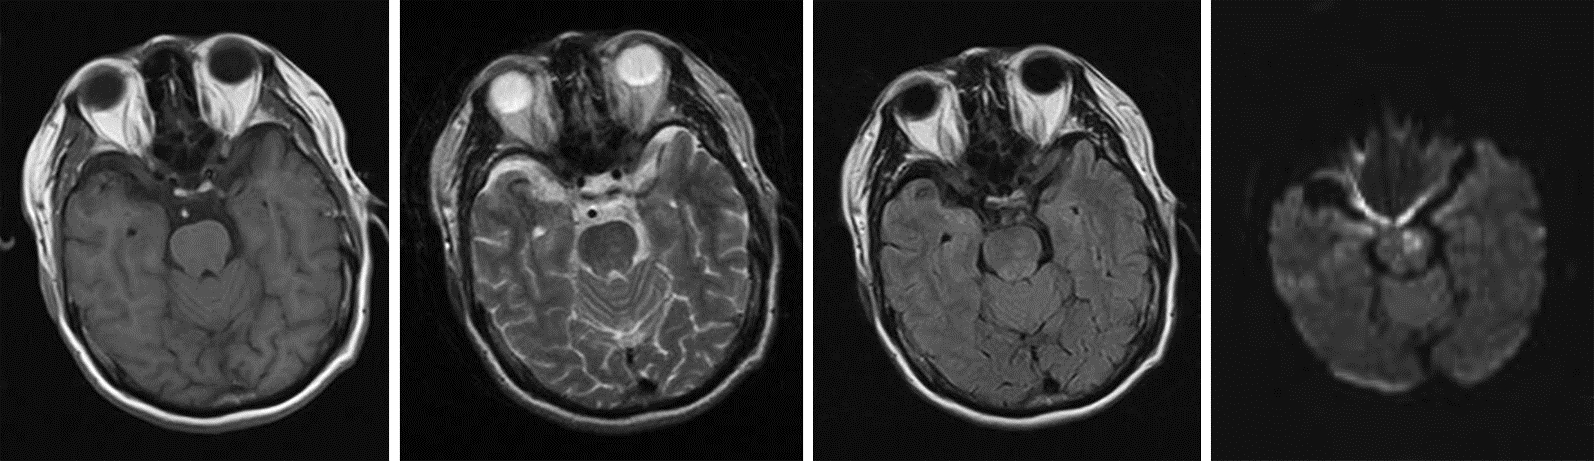

入院辅助检查:血尿便常规、肝功能、凝血功能、血沉、超敏CRP、RF、ASO、输血常规未见明显异常。尿酸 584.0 μmol/L;甘油三酯 1.83 mmol/L。心电图、心脏彩超、颈部血管彩超未见明显异常。MRI显示脑桥上段左侧腔梗灶。DWI显示脑桥上段左侧急性梗死(图 1)。MRA未见明显血管狭窄(图 2)。诊断:脑干梗死,高血压病,痛风。

| 图 1 患者头颅MRI。A:T1加权像显示脑桥上段中线左侧稍长T1信号;B:T2加权像显示脑桥上段中线左侧稍长T2信号;C:FLAIR显示脑桥上段中线左侧稍高信号;D:DWI显示脑桥上段中线左侧高信号。 |

据文献报导,一侧性前核间性眼肌麻痹多见于脑干血管性疾患,也多见于多发性硬化、脑干炎症和脑干肿瘤。Keane[1]统计了410例核间性眼肌麻痹患者,其中157例由梗死造成。张文萃[2]对120例前核间性眼肌麻痹患者进行病因统计发现,脑桥出血4例,基底动脉或其分支闭塞72例,多发性硬化16例,脑桥肿瘤8例,脑桥炎症7例,其他病因13例。核间性眼肌麻痹可为脑干背侧梗死的主要症状,也可为唯一症状,发病机制可能为:①由于脂质透明样变或纤维玻璃样变所引起的穿支动脉终末部分病变,即TOAST分型中的腔隙性脑梗死;②主干动脉分出穿支动脉入口处发生动脉粥样硬化病变,引起管腔狭窄或闭塞[3]。高血压是腔隙性脑梗死的直接原因,糖尿病、脂代谢障碍亦可引起本病,糖尿病引起的微血管病变及血液高凝状态是腔隙性脑梗死的独立危险因素[3]。孤立性一侧前核间性眼肌麻痹临床少见,多为个案报道,临床恢复较快[4]。孙奉辉等[5]报道一例头颅 MRI明确脑桥背部偏左侧内侧纵束梗死引起的前核间性眼肌麻痹患者,治疗一周后症状明显好转。本例患者临床表现双眼向右侧注视时,左眼内收不全,右眼外展正常,伴右眼水平眼震,向左侧注视时眼球运动正常,辐辏反射正常,符合前核间性眼肌麻痹,头颅 MRI 检查显示脑桥与中脑交界处背侧中线偏左侧可见稍长T1、T2,FLAIR高信号,DWI高信号,结合症状、体征和头颅MRI 检查结果,诊断急性脑干梗死(前核间性眼肌麻痹)。患者既往有高血压病史,未规律治疗,辅助检查见血脂升高,高血压病、血脂异常为主要危险因素,引起脂质透明样变或纤维玻璃样变导致穿支动脉闭塞。患者治疗上予以抗血小板聚集、调脂、改善循环和神经保护等处理,症状迅速好转。